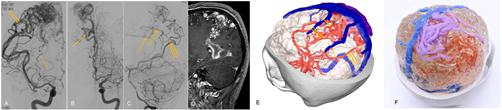

³í¹®¿¡ ¾²ÀÎ ³úÇ÷°üÁúȯ ȯÀÚ ÀǷ῵»ó ±â¹Ý 3D¸ðµ¨¸µ ¹× 3DÇÁ¸°ÆÃ case 1. ³úµ¿¸Æ

case 2. µ¿Á¤¸Æ±âÇü

case 3. ÇØ¸é±âÇü

À̹ø¿¡ °ø°³µÈ ³í¹®¿¡ µû¸£¸é ´ëÇ¥ÀûÀÎ ÁßÁõ ³úÇ÷°ü ÁúȯÀÎ µ¿¸Æ·ù, ÇØ¸é±âÇü, µ¿Á¤¸Æ±âÇü ȯÀÚ±º ¼ö¼ú¿¡ ÀǷ῵»ó ±â¹Ý 3D¸ðµ¨¸µ ¹× 3DÇÁ¸°ÆÃ ±â¼úÀ» Àû¿ëÇÒ °æ¿ì º´º¯°ú Ç÷°ü ±¸Á¶¸¦ ÈξÀ Á¤È®ÇÏ°Ô ½Äº°ÇÒ ¼ö ÀÖ´Ù.

ƯÈ÷ ÀûÀýÇÑ ¼ö¼ú °èȹ ¹× ½Ã¹Ä·¹À̼Ç, Á¢±Ù ¹æ½Ä ¼öÁ¤, ¼ö¼ú½Ã°£ ´ÜÃà µî ȹ±âÀûÀÎ È¿°ú¸¦ °ÅµÑ ¼ö ÀÖ´Â °ÍÀ¸·Î È®ÀεƴÙ.

¿¬±¸¸¦ ÁÖµµÇÑ Á¶¿ø»ó ¼­¿ï´ëº´¿ø ½Å°æ¿Ü°ú ±³¼ö´Â "ȯÀÚ±º Áß¿¡¼­ ¼ö¼ú ³­µµ°¡ °¡Àå ³ôÀº Áõ·Ê¸¦ ´ë»óÀ¸·Î ÀÓ»óÀ» ÁøÇàÇßÀ¸¸ç, 3Â÷¿ø °á°ú¹°ÀÌ ¼ö¼ú Àü·« ¼ö¸³¿¡ °áÁ¤ÀûÀÎ µµ¿òÀ» ÁÙ ¼ö ÀÖ´Ù´Â °ÍÀ» È®ÀÎÇß´Ù"°í ¹àÇû´Ù.

Á¶ ±³¼ö´Â ƯÈ÷ "ÇØ´ç ÁúȯÀÇ »À¿Í Ç÷°ü ±¸Á¶ »Ó ¾Æ´Ï¶ó ³ú¸·Á¶Á÷, ³ú½Å°æ, Á÷°æ 1mm ¼öÁØ ¹Ì¼¼Ç÷°ü±îÁö ±¸ÇöÇÑ °ÍÀº ¼¼°è ÃÖÃÊ"¶ó¸ç "ÁøÀϺ¸ÇÑ ¸ÞµðÄþÆÀÌÇÇ 3Â÷¿ø ±¸Çö ±â¼úÀÌ ÀÖ¾ú±â¿¡ °¡´ÉÇß´Ù"°í µ¡ºÙ¿´´Ù.